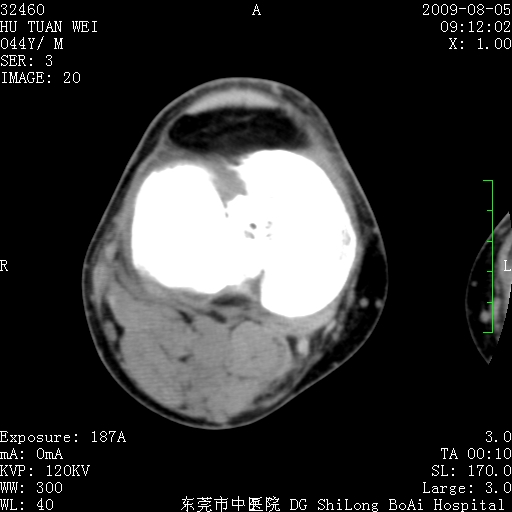

中年男性,膝韧带损伤术前检查!其他病史不清粗,不是我接手病人、且出院了!

1、股骨下段囊状膨胀性病变,边缘硬化明显,内多个残留骨棘呈多房型改变,囊腔密度较高无钙化,膝关节滑膜囊增厚,密度增高,关节腔少量积液。考虑:邻关节囊肿、退变性囊肿(软骨下囊肿)、着色性绒毛结节性滑膜炎、abc、骨巨、良性纤维组织细胞瘤等鉴。虽然年龄偏大,部位于骨端,但有外伤史,本人还是倾向于动脉瘤样骨囊肿(abc)可能性大。邻关节囊肿及软骨下囊肿次之考虑。

2、胫骨髁间棘撕脱骨折,交叉韧带损伤可能;

3、关节退行性改变。

病理结果:色素沉着绒毛结节性滑膜炎

感谢反馈病理结果!本病为慢性关节病变。以关节滑膜高度增生、绒毛结节形成伴含铁血黄素趁着为特点。病因:有炎症、肿瘤、外伤关节出血、代谢障碍、变态反应及感染等学说。增强扫描呈关节腔内单个或多个强化的软组织结节影或滑膜不规则增厚伴关节积液为本病的特征性表现。